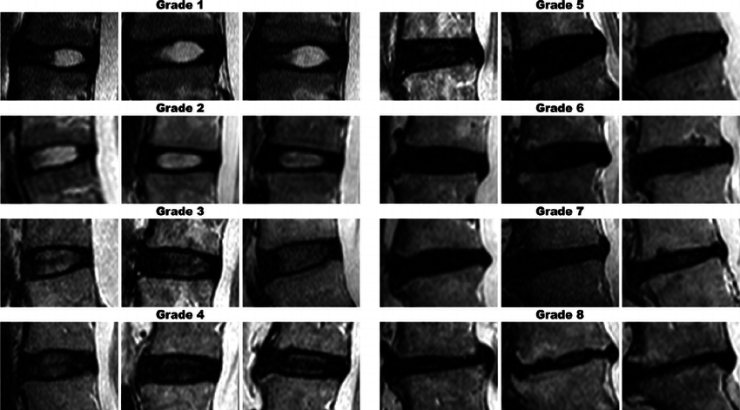

- Tonosu j, et al. found that on lumbar MRI findings consistent with Pfirrmann grade ≥3, disk bulging, and High Intensity Zones may be one of the predictive signs of recurrent severe LBP.[iv]

Figure 1. Image reference panel shows increasing severity of disc degeneration. The pertinent features of each grade are described in Table 1. Three images reflect the inherent variability across each grade.

From: Griffith, J.F., Wang, Y., Antonio, G.E., Choi, K.C., Yu, A.B., Ahuja, A.T., & Leung, P. (2007). Modified Pfirrmann grading system for lumbar intervertebral disc degeneration. Spine, 32 24, E708-12.